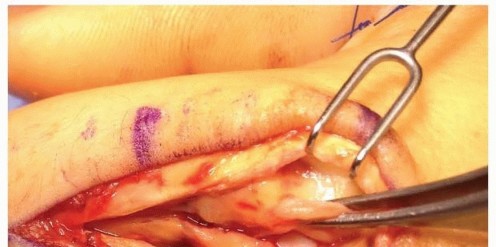

DORSAL APPROACH FOR FIXATION

TECH FIG 4 • (continued) G,H. Motion at 6 weeks after surgery. The periosteum is elevated at the fracture site to assist with assessment of fracture reduction. As much of the interosseous muscle is left attached to the metacarpal as feasible to preserve blood supply to the bone.The fracture is reduced and provisionally stabilized with reduction clamps (TECH FIG 4D).

LAG SCREW FIXATION

Long oblique and spiral fractures whose lengths are at least twice the diameter of the bone at the level of the fracture are amenable to limited fixation with screws only (see TECH FIG 4A-C).Appropriately sized lag screws (1.4 to 2.7 mm) are placed. Typically, two or three screws are used (TECH FIG 4E,F).The first screw is placed perpendicular to the fracture in order to compress it and the second screw is placed perpendicular to the bone to resist longitudinal forces.In order to get proper compression with a lag screw construct, it is important to overdrill the near cortex.When using a 2.0-mm screw system, a 1.5-mm drill bit is used to drill both cortices. The near cortex is then overdrilled with a 2-mm drill bit.A countersink is used to maximize contact between the head of the screw and the bone. The size of the screw is measured and an appropriately sized screw is placed.The periosteum and interosseous muscle fascia are reapproximated to cover the screws. The juncturae tendinum are repaired and the skin is closed in standard fashion.The hand is then immobilized with the MP joints flexed 70 to 90 degrees with a forearm-based splint. Early motion can be started as early as 4 to 7 days, depending on fracture stability (TECH FIG 4G,H).